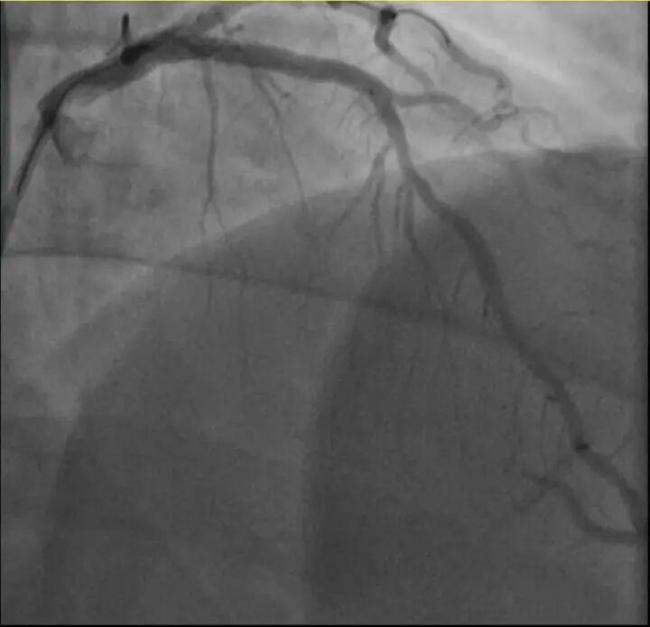

孙先生是一位羽毛球教练,身高173cm,体重约90KG。一年前,他因胸闷就诊时被查出心脏右冠中段、远端钙化斑块,以及心脏三支主要血管之一前降支中段60%狭窄。当时考虑到没有三高的危险因素(可能为早发冠心病家族史),孙先生坚信自己可以通过运动恢复健康,因此拒绝了介入治疗,只接受药物治疗。经过一年的努力,他的体重从96KG减到了90KG。然而,近日在带孩子练习羽毛球时,孙先生亲自上场挥杆仅10分钟左右,就因心前区剧烈绞痛被送进了急诊。医生分析,剧烈运动导致这位患者心脏的不稳定斑块破裂,进而造成前降支近段次全闭塞。所幸送医及时,孙先生的身体险情被化解。

另一位38岁的钱先生也有类似遭遇。钱先生的血糖一直偏高,服药后控制不佳,但年轻的他并没有太在意。周末,他和孩子爬了一座山,隔天就因突发胸骨中段压榨性疼痛被送到了急诊,最后被证实也是心梗——心脏三支主要血管之一回旋支远段次全闭塞。医生介绍,钱先生来院时血糖12.79mmol/L(正常空腹值应该在3.9~6.1mmol/L),甘油三酯也超标。三高是导致动脉粥样硬化的主要危险因素,在冠状动脉粥样硬化早期,血管狭窄可能并不严重,但在运动、情绪激动等情况下,心肌耗氧量增加,可能导致心梗等急性心肌缺血事件。所幸及时治疗,钱先生也转危为安。